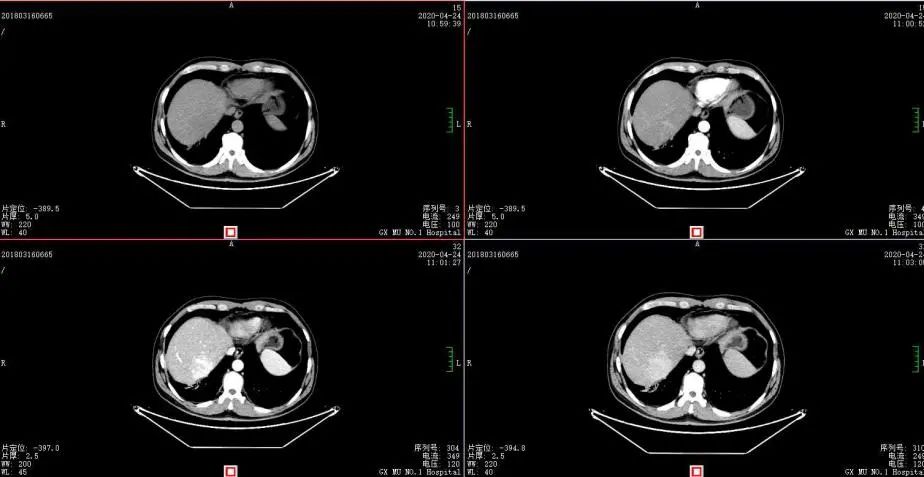

2020年4月复查:持续PR

增强CT示:肝硬化

肝异常强化灶

考虑酒精性肝硬化可能性大,未基线使用替吉奥维持治疗。

胃癌并肝转移化疗后,肝内转移灶大致同期;

慢性肝病,脾大、门脉高压(食管下段-胃底静脉曲张);